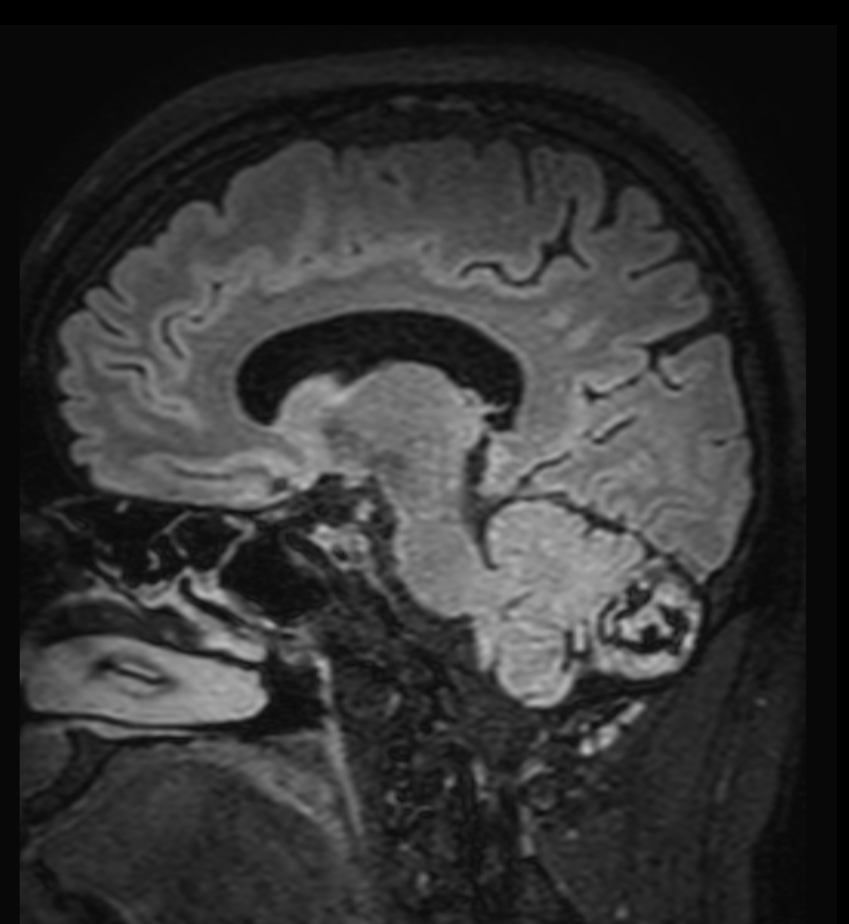

Patient with a lesion in the cerebellum. The ExamCard includes Compressed SENSE to accelerate the entire exam and techniques for motion reduced imaging (MultiVane XD), 3D imaging to acquire high resolution data in multiple directions, 3D susceptibility weighted imaging (SWIp), angiography sequences (Time-of-Flight and Contrast-Enhanced MRA with both arterial and venous phases), DTI with MultiBand SENSE to acquire a high number of diffusion directions in a short scan time and EPIC Brain to bring down any residual distortion.

3D T1w FFE FatSat post-gado (reformat) Compressed SENSE